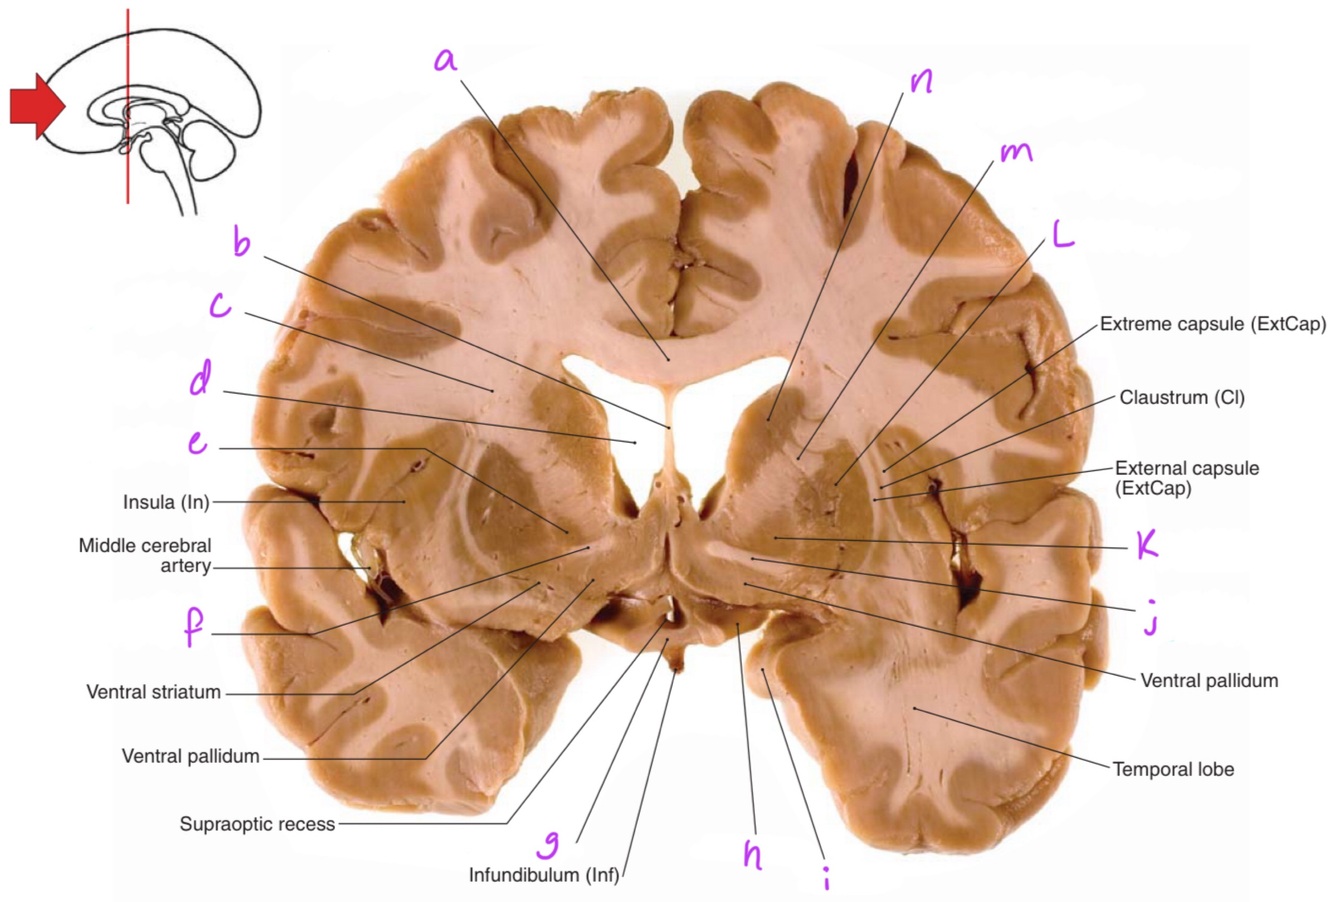

1

a

body of corpus callosum

b

Anterior horn of lateral ventricle

3

c

4

d

Q

g

Putamen

2

Perfectly

How well did you know this?

Not at all

11

13

e

15

17

i

19

k

21

m